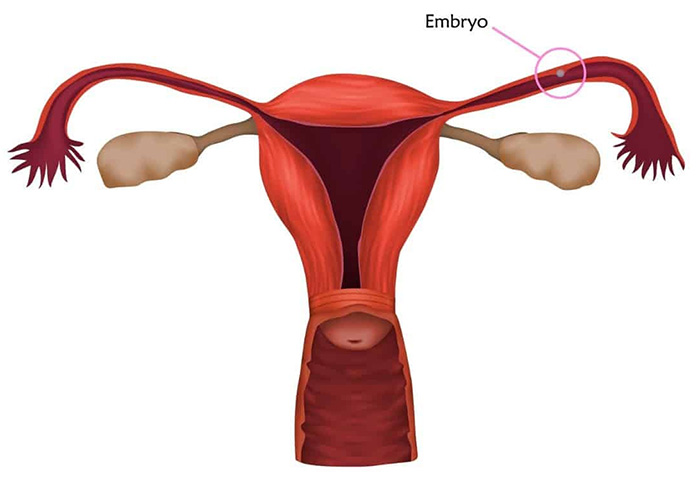

پس از تخمک گذاری، تخمک سفر پنج روزه خود را از طریق لوله فالوپ به سمت رحم آغاز میکند. همانطور که تخمک از طریق لوله فالوپ حرکت میکند، سطح پروژسترون، هورمون دیگری، در بدن افزایش مییابد که به آماده سازی پوشش رحم برای بارداری کمک کند.